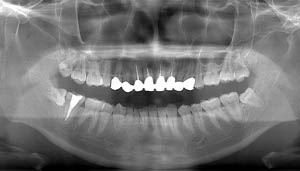

右下の親知らずが疼く症例

- 抜歯前写真(レントゲン)

- 抜去歯の写真(CT画像)

| 年齢 | 30代・女性 |

|---|---|

| 主訴 | 右下親知らずが疼く |

| 親知らずの生え方 | 横向きに生えている |

| 抜歯時間 | 40分 |

| 費用 | 約8,000円(保険診療、CT代含む) |

| 抜歯内容 | 右下の親知らずは横向きに生えて埋まっているため、麻酔をし親知らずの奥に切開を入れて歯ぐきを開き、歯を囲んでいる骨を削り歯の頭部分を割って出してから、残った根の部分を取り出して抜歯は終了しました。 歯ぐきを切った部分は糸で縫っています。このケースでは根の先端が神経に近く麻痺のリスクがありましたが事前にCTを撮影し、神経との位置関係を確認していたため、麻痺が残ることはありませんでした。 約1週間後に糸取りを行い、その際も多少の痛みや腫れはありましたが後日その痛みも無くなりました。 |